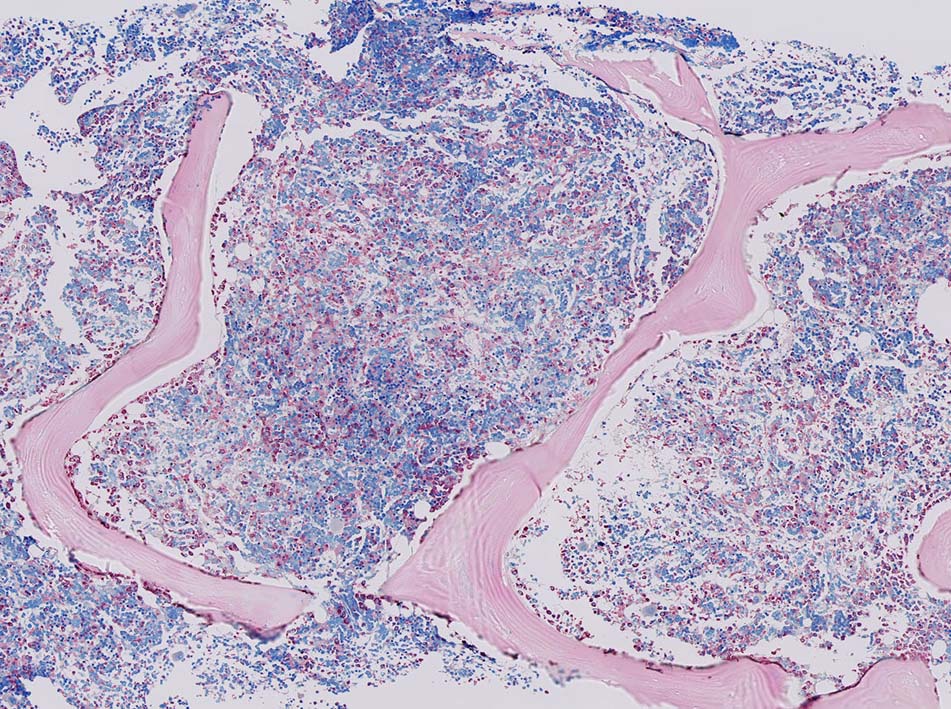

• 肝, 脾, 骨髄では類洞ないし静脈洞浸潤が顕著。脾臓では赤脾髄領域を中心に拡張した静脈洞内に腫瘍細胞が浸潤する。

• 肝臓では門脈域は通常保たれる。脾臓では白脾髄は通常保たれている。

骨髄への腫瘍細胞浸潤はintertrabecular patternで, 腫瘍細胞は小集簇巣を形成して散在性に認められた. HE, ASD-Giemsaのみでの浸潤, 増殖の確定はなかなか難しいようです.

ASD-GiemsaではASDに染まらない(陰性の)あやしい細胞塊があるように見える. 細胞小塊はCD3陽性.

免疫染色でCD3陽性となる細胞集塊のASD-Giemsa像. 肝類洞内浸潤細胞に比較して核, 細胞が紡錘形の傾向を示している.